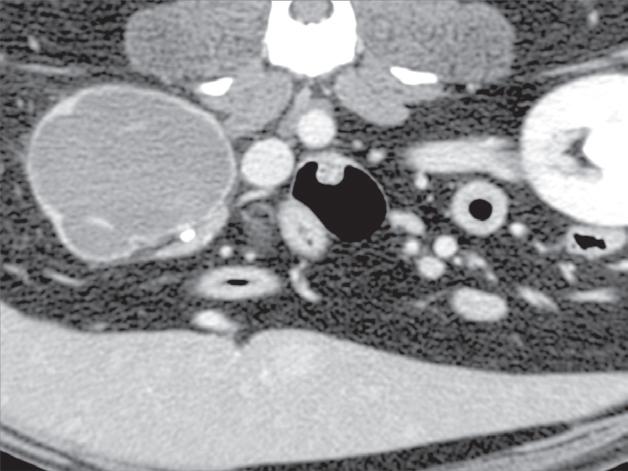

Badanie wykonano u 7-letniego rottweilera z rozpoznanym guzem nadnercza oraz nagłymi objawami dyskomfortu jamy brzusznej. Obrazy na ryc. a–c uporządkowano od strony doczaszkowej do doogonowej. Nadnercze prawe jest powiększone (a, d – otwarty grot strzałki) i ma widoczną ekscentryczną komponentę torbielowatą o densyjności płynu, która rozchodzi się doogonowo (a, b – strzałki). Tkanka miękka rozrostu oraz torebka nadnercza wykazują obwodowe wzmocnienie pokontrastowe. Torbielowata komponenta zmiany rozrostowej widoczna na obrazie odpowiada krwotokowi, który rozciąga się doogonowo w przestrzeni zaotrzewnowej (d). Dobrzusznie od zmiany widoczny jest moczowód (b – grot strzałki). Diagnoza makroskopowa i histologiczna została potwierdzona po chirurgicznym usunięciu zmiany (e – strzałka). Proszę zwrócić uwagę na porównanie obrazu TK zmiany (d) z wyciętym preparatem makroskopowym (f)